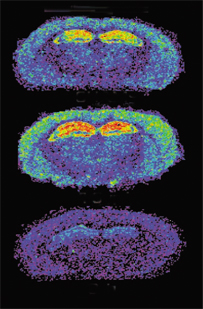

Using a radioactively labeled compound that binds to the active form of the primary glutamate receptor, the investigators analyzed brains slices from mice at different times after each had received a traumatic blow to the head. As expected, an initial burst of receptor activity appeared in the minutes after the injury, presumably from glutamate released by directly damaged cells. In the following hours, however, the activity of this glutamate receptor declined to below-normal levels, Biegon’s team reports in the April 6 Proceedings of the National Academy of Sciences.